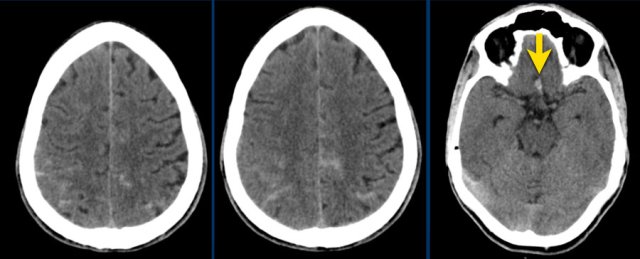

Here another example of a nonaneurysmal perimesencephalic SAH.

Left image: NECT showed a small amount of subarachnoidal blood anterior to the brainstem.

Right image: more cranially, the pentagon, ambiens cistern and the proximal part of Sylvian’s fissures, did not show any blood.

This is a typical presentation of nonaneurysmal perimesencephalic SAH.

The blood is solely located around the brainstem.